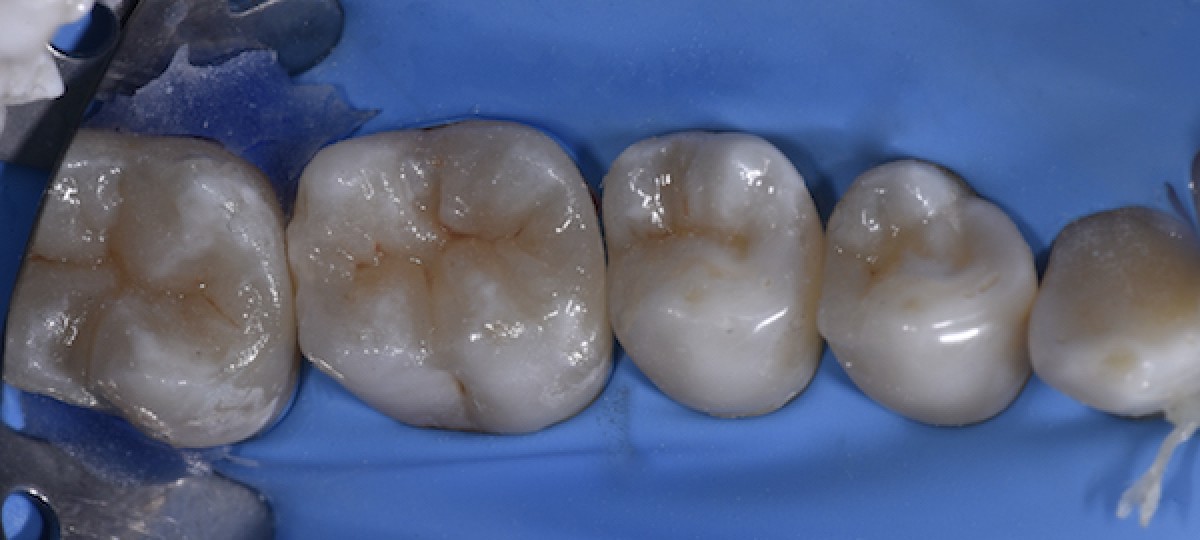

Immediately after light curing under glycerin, before polishing (Fig.12)